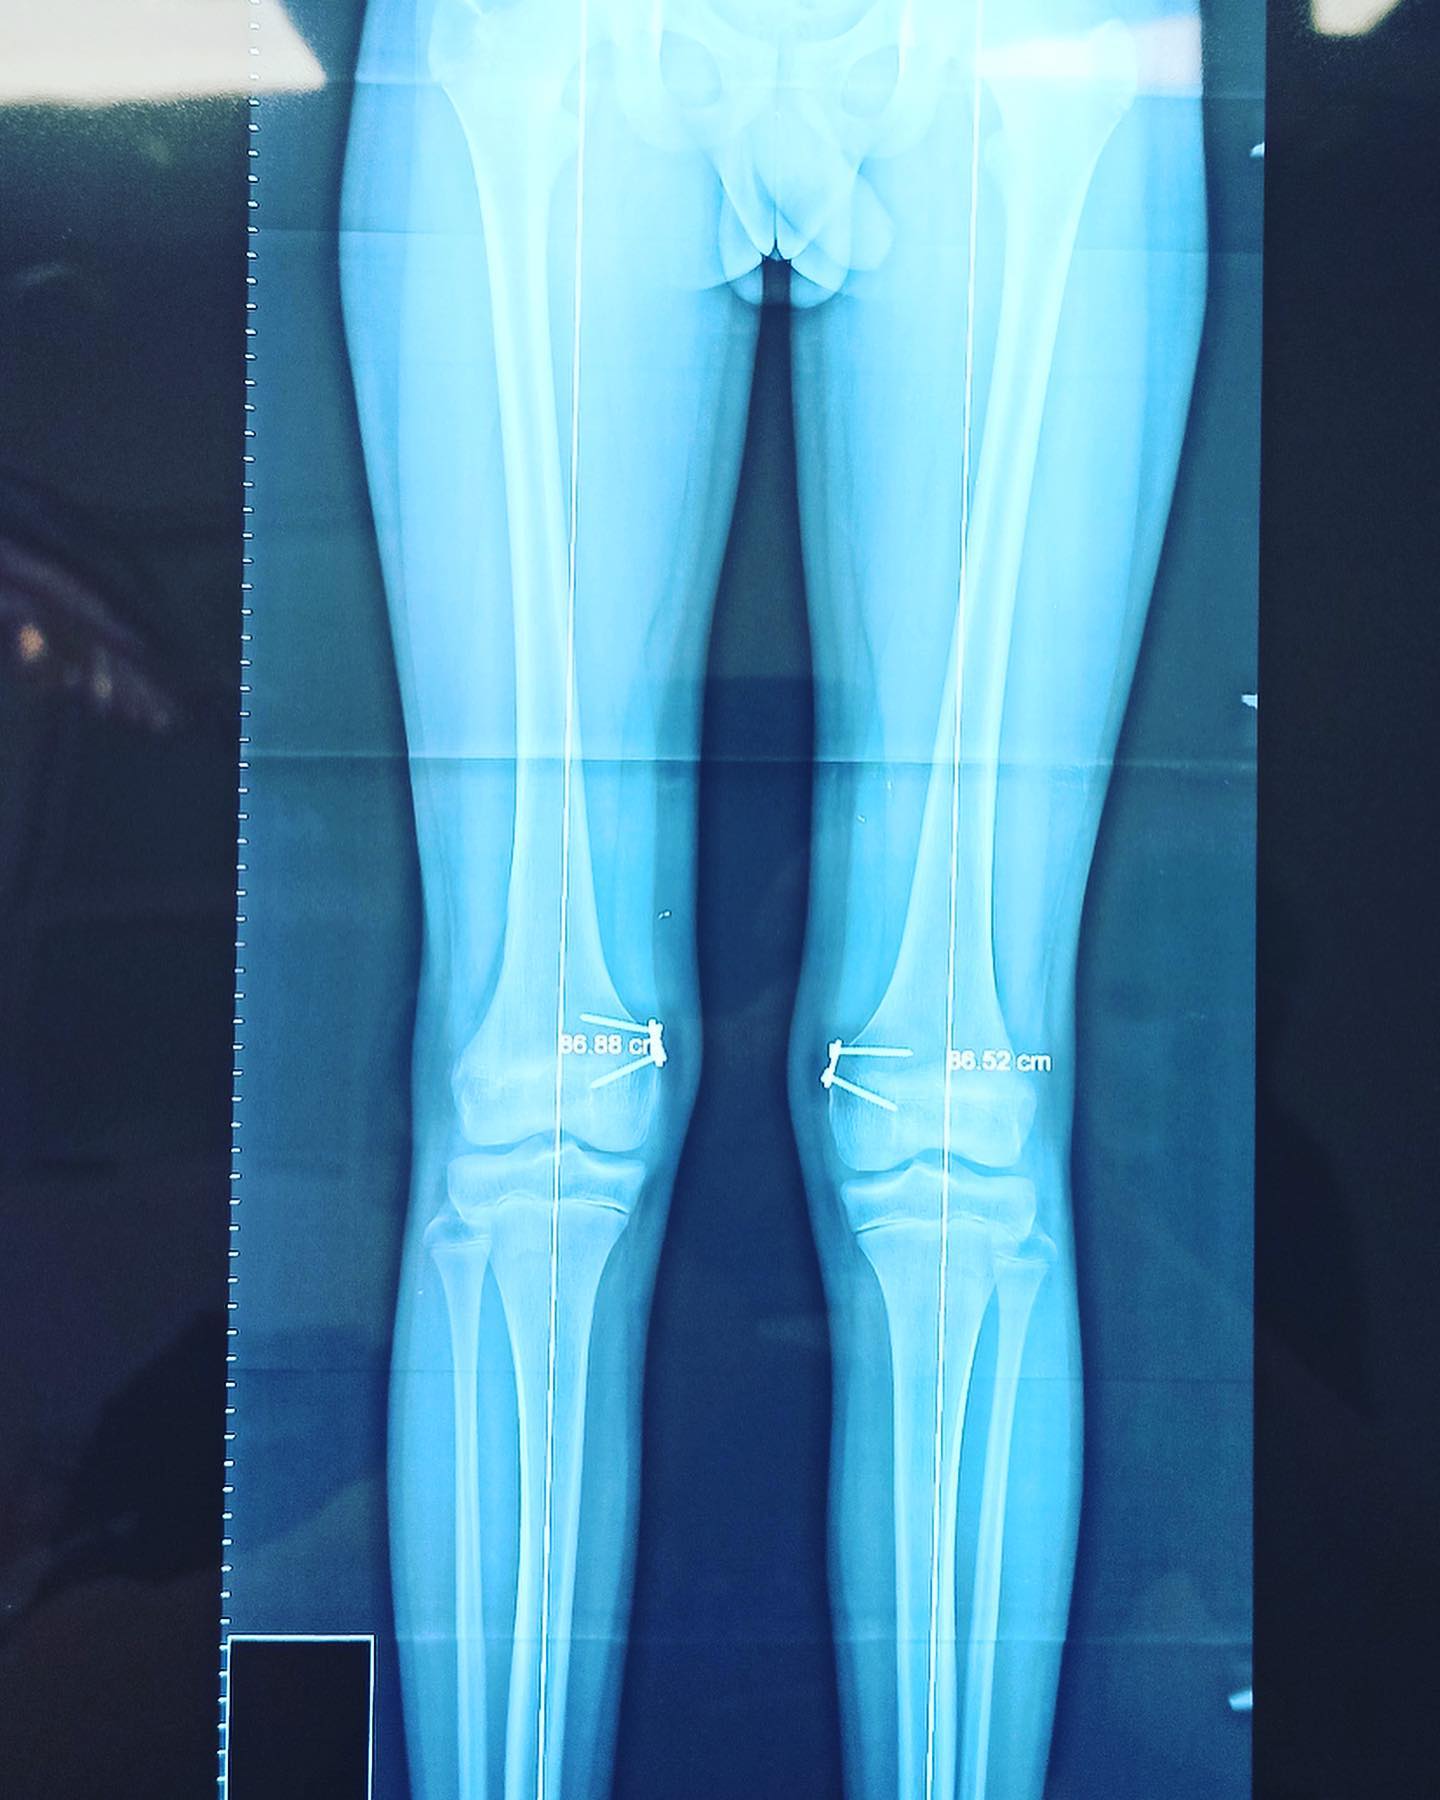

Rodillas en valgo

Él es mi paciente Isaac, de 13 años. Acudió a consulta hace 2 años por una deformidad en valgo de sus rodillas. Le realicé un tratamiento para corregir la deformidad y ahora lo doy de alta. #rodillasvalgas #correccióndeformidadesangulares